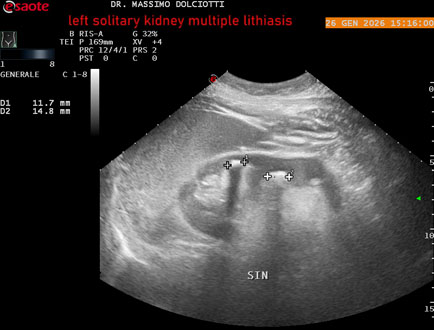

Data inserimento: 29/01/2026

Ecografia del: 26/01/2025

Strumento: Esaote MyLab Eight

Sonda: Conevx Multifrequenza 1-8 MHz

Età Paziente: M 78 anni

Motivazione dell'esame: follow up di litiasi al rene sinistro, in paziente sottoposto a nefrectomia destra.

Commento all'esame: le immagini ed il video documentano il rene sinistro in sede, di ecostruttura disomogenea per evidenza di multiple formazioni litiasiche al pielone superiore, delle dimensioni di 15,9 mm, al pielone medio di 17,5 mm e al pielone inferiore di 18,9 mm e morfovolumetria normale, con diametro bipolare di 115 (v.n. 90-120 mm) x 54 mm e parenchima renale dello spessore di 17 mm ( v.n. > 13 mm).

Conclusioni: litiasi multipla del monorene sinistro (multiple lithiasis of the left solitary kidney).

In collaborazione: Dr.ssa Marica Manfredi - Ancona, Dr. Ilir Qose - Ancona

Presentazione: Dr. Massimo Dolciotti - Ancona

Elaborazione digitale: Andrea Dini - Ancona